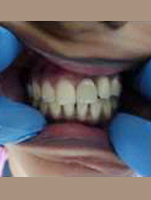

Post Operation

After Placement of Prosthesis

Powered By - www.calcuttayellowpages.com